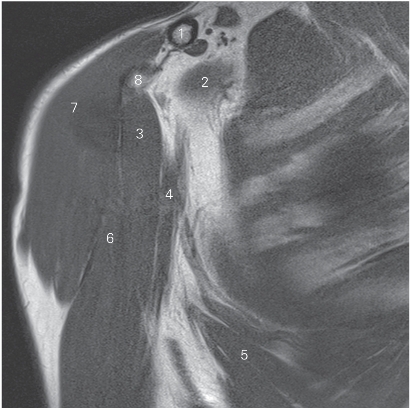

图4-20 经肱二头肌短头的矢状断层MR T2WI FS

1 喙肩韧带 coracoacromial ligament 2 冈上肌 supraspinatus

3 肩胛冈 spine of scapula 4 肱骨头 head of humerus

5 冈下肌 infraspinatus 6 小圆肌 teres minor

7 三角肌 deltoid 8 肱三头肌 triceps brachii

9 胸大肌 pectoralis major

10 肱二头肌短头 short head of biceps brachii

11 肩胛下肌 subscapularis

12 肱二头肌长头 long head of biceps brachii